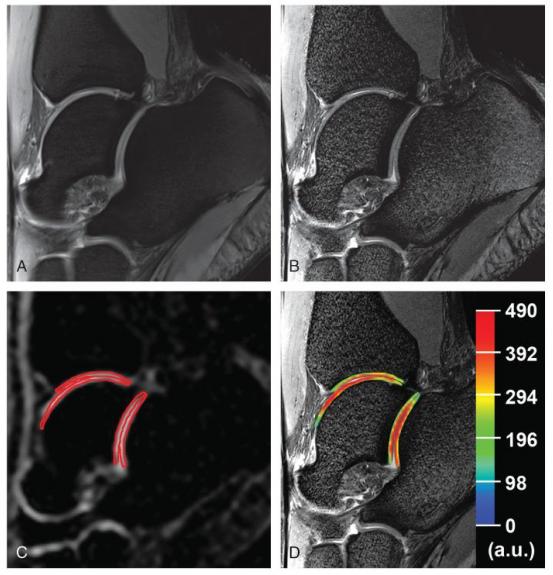

Протонный и соответсвующие натриевые снимки голеностопного сустава 23-х летней женщины в норме. А. Сагиттальный 2D-TSE снимок, взвешенный по протонной плотности с подавлением сигнала от жира и низким разрешением (0.31×0.31×3.0 мм3). В. Сагиттальный 2D-TSE снимок, взвешенный по протонной плотности с подавлением сигнала от жира (WIP 729C; Siemens, Erlangen, Germany) и высоким разрешением (0.27×0.27×1.5 мм3). С. Сагиттальный 3D-GRE натриевый снимок с красными конутрами, которые предсталяют исследуемую область при оценке хрящей в голеностопном и подтаранном суставах. D. Цветное cSI картирование натрия в хрящах, наложенное на соответствующий морфологический снимок.

Zbýň Š, Brix MO, Juras V, et al. Sodium Magnetic Resonance Imaging of Ankle Joint in Cadaver Specimens, Volunteers, and Patients After Different Cartilage Repair Techniques at 7 T: Initial Results. Investigative radiology. 2015;50(4):246-254. doi:10.1097/RLI.0000000000000117.